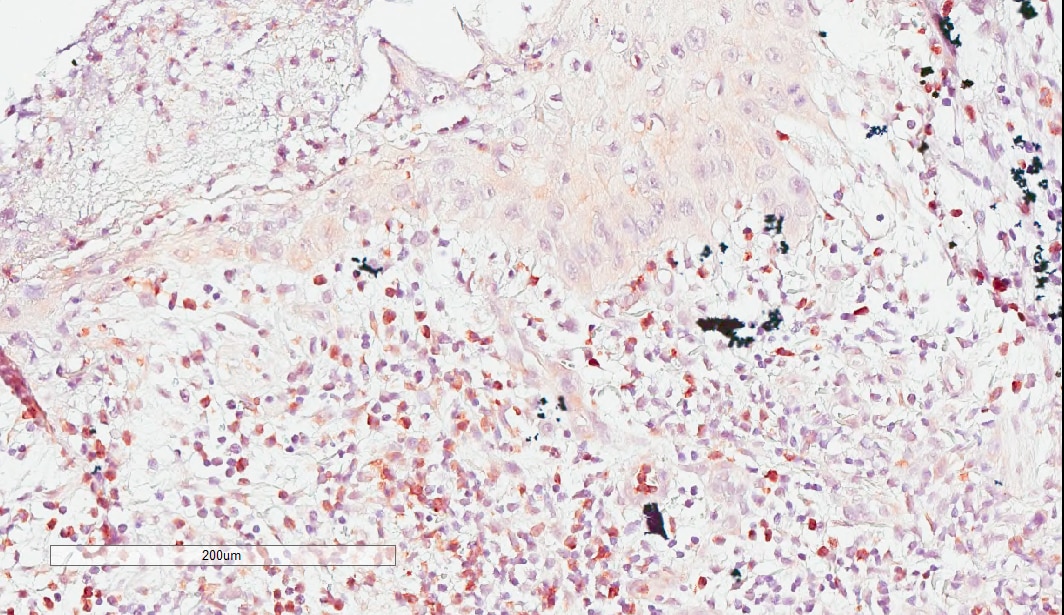

Immunohistochemistry-Paraffin: Granzyme K Antibody [NBP2-49387] - Staining of human spleen shows strong granular cytoplasmic positivity in cells in red pulp.